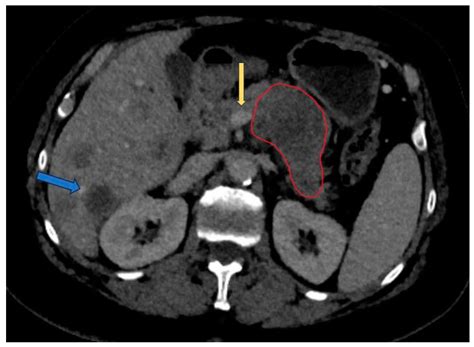

Interpreting the results of a pancreas CT scan requires expertise in radiology. Radiologists look for various signs and abnormalities that can indicate different conditions. Some key findings include:

• Pancreatic Cancer: CT scans can reveal masses or tumors in the pancreas, which may appear as areas of increased density or irregular shapes.

• Pancreatitis: Inflammation of the pancreas can cause swelling and changes in the organ's texture, which are visible on CT scans.

Radiologists also evaluate the surrounding structures, such as the liver, spleen, and blood vessels, to determine if the disease has spread or affected other organs.